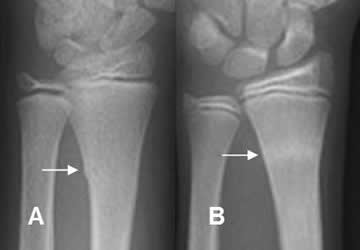

Fig 63 A. Fractura en torus.

A: y B: Rx AP. Cortical “arrugada” en el tercio distal del radio, por fracturas en torus.

Fig 63 B. Fractura en torus.

A y B: Rx AP. Fractura en torus del radio distal. En la proyección de control, se identifica imagen densa en el lugar de la cicatrización.